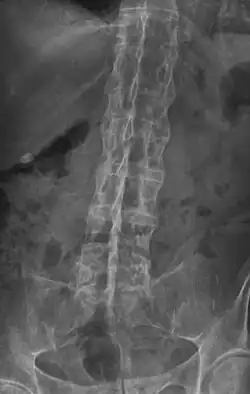

X-ray showing "bamboo spine" in a person with ankylosing spondylitis -